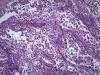

Опухоль легкого |

Карциноид...

Аденокарцинома со стелющимся типом роста (lepidic)

Тоже склоняюсь к бронхиолоальвеолярному раку.

Уважаемый Медик, добрый вечер! Поясните, пожалуйста, в чем существенная разница между БАР и предложенным мной вариантом? В своей работе я использую классификацию 2015 года, в которой БАР нет, это устаревший термин. Верно, с 2015г..БАР нет. В данном случае Аденкарцинома, lepidic тип👏 |